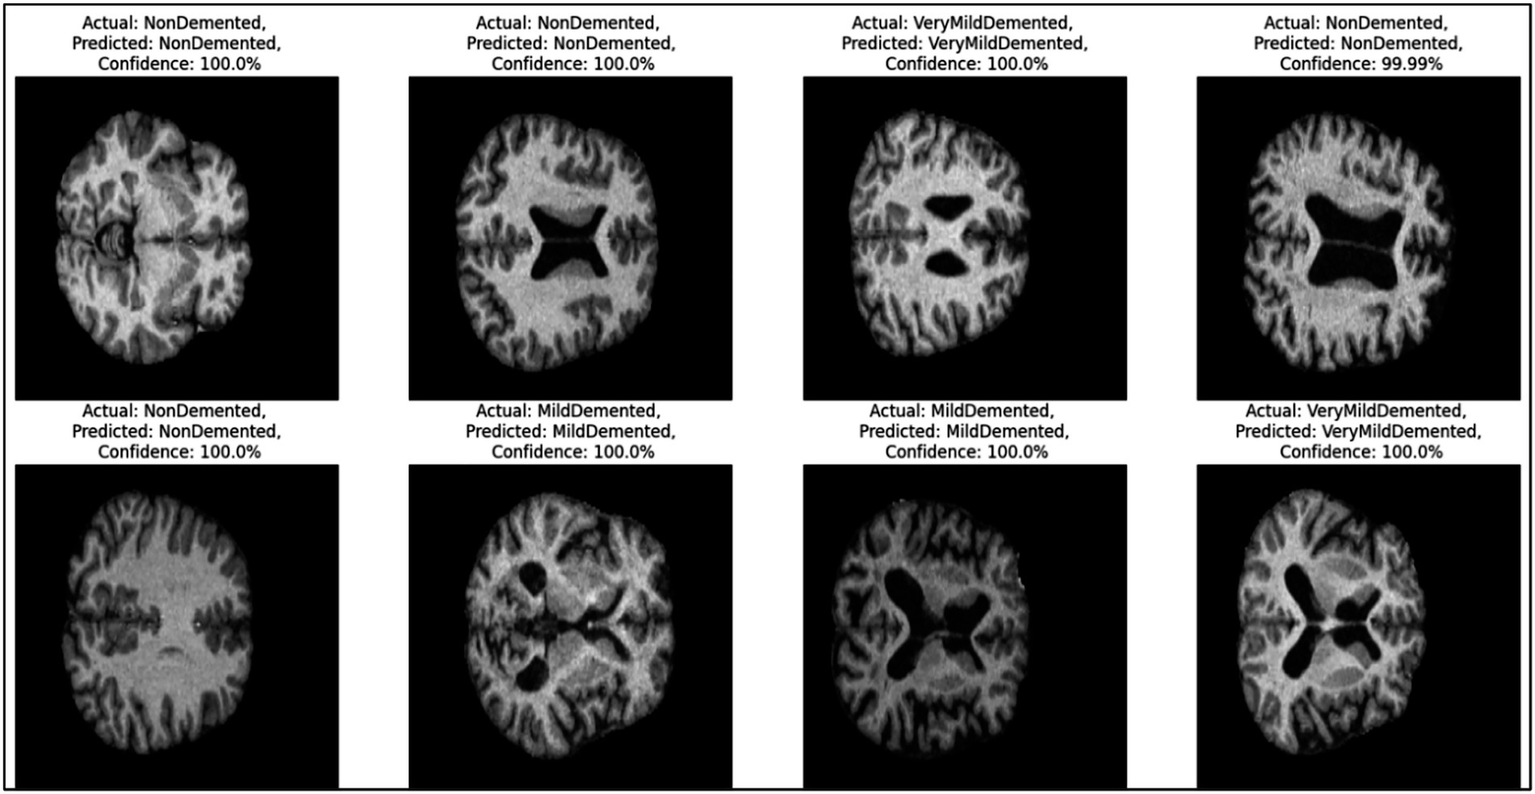

Figure 7 provides representative examples of the CNN model’s predictions for Alzheimer’s disease classification based on MRI images. Each sub-image includes the actual label, predicted label, and the confidence score of the prediction, showcasing the model’s ability to classify different stages of Alzheimer’s disease with high accuracy.

Figure 7

Example predictions generated by the CNN model.

On the left side, the first two rows show “Non-dementia” cases, where both the actual and predicted labels are “Non-dementia.” The confidence score for these predictions is 100%, reflecting the model’s absolute certainty. These images indicate the structural patterns that the model associates with the absence of dementia. Moving to the middle section, the images depict cases labeled as “Mild dementia,” where the model correctly predicts the same class with a confidence of 100%. These samples demonstrate the model’s ability to identify the subtle features of mild dementia from the MRI scans. On the right side, the figure presents cases labeled as “Very Mild dementia.” Again, the model correctly predicts the same class with confidence scores either at 100% or very close (e.g., 99.99%). These predictions highlight the model’s precision in distinguishing between different early stages of dementia.